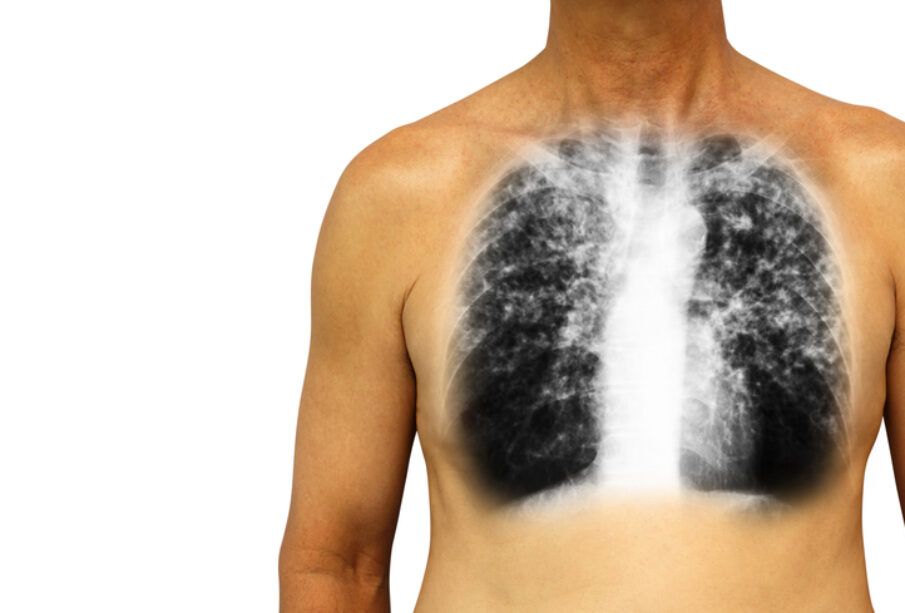

- Ακτινογραφία θώρακος: Δείχνει αν υπάρχει διόγκωση της καρδιάς ή των πνευμονικών αρτηριών και βοηθά στον αποκλεισμό άλλων παθήσεων της καρδιάς ή των πνευμόνων.